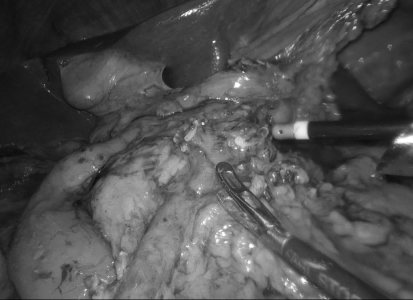

手术如期进行。如术前所预料,腹腔镜探查可见腹腔内粘连明显,周边组织界限模糊。手术团队凭借丰富的经验和精湛的技艺,耐心细致地一点一点分离粘连,如同“抽丝剥茧”,逐步恢复了正常的解剖层次。在清晰暴露手术视野后,团队严格按照根治原则,精准完成了右半结肠系膜的游离、血管的高位结扎、淋巴组织的彻底清扫以及消化道重建。整个手术过程流畅,出血量极少,成功避免了邻近脏器的副损伤。